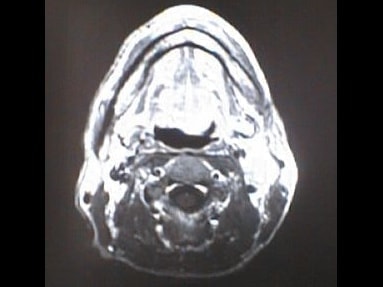

MRI画像比較

入院当時MRI画像①

入院3か月後癌消滅MRI画像①

入院当時MRI画像②

入院3か月後癌消滅MRI画像②

入院当時MRI画像③

入院3か月後癌消滅MRI画像③

入院当時MRI画像④

入院3か月後癌消滅MRI画像④